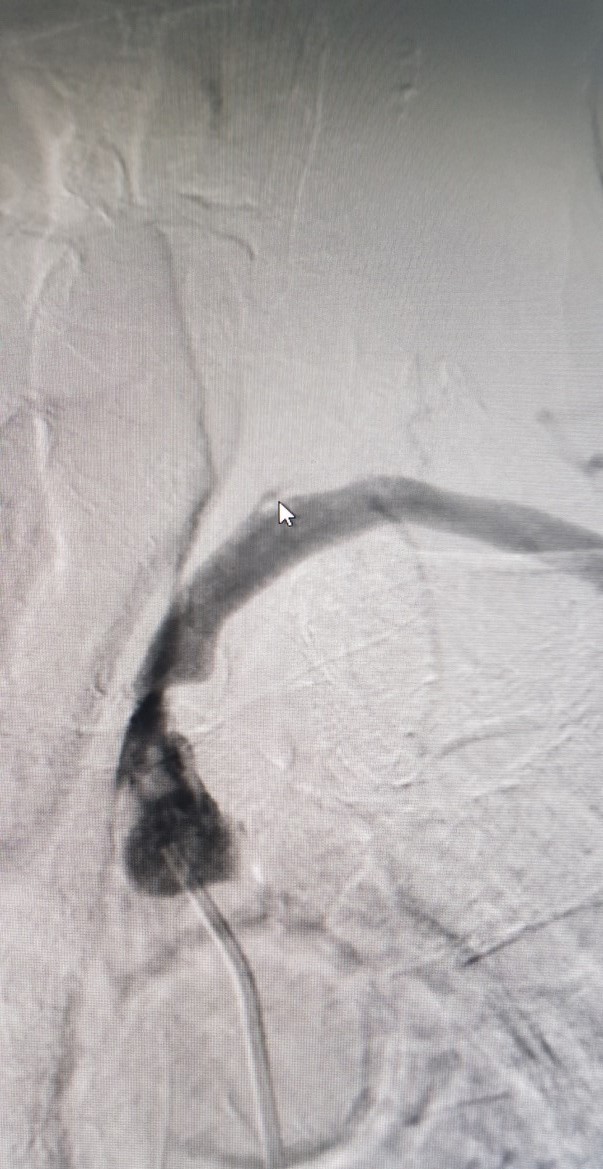

Trước can thiệp

Hình ảnh can thiệp động mạch dưới đòn tại Bệnh viện Đa khoa Tỉnh Quảng Trị